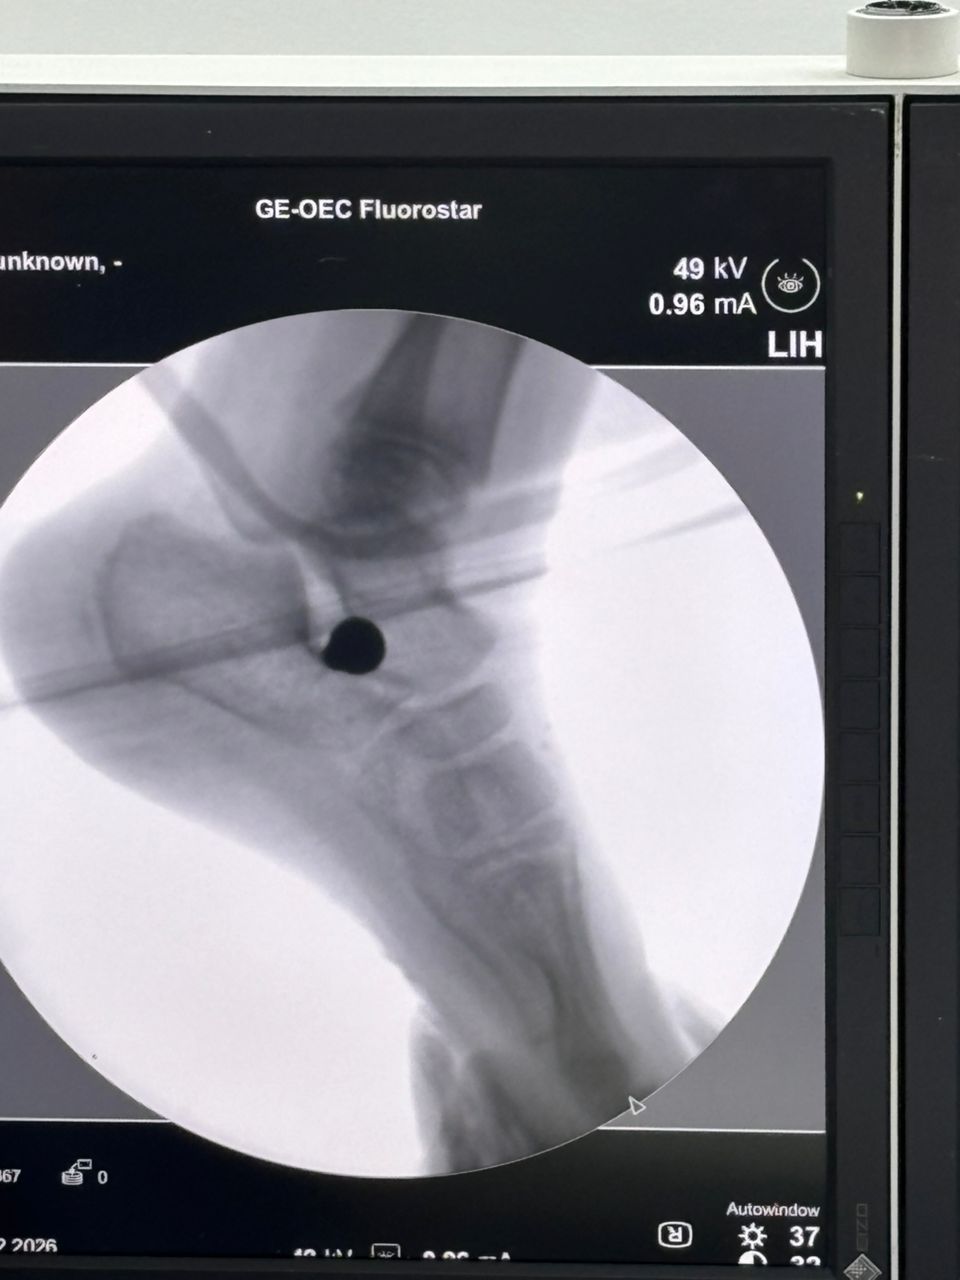

Fulkerson